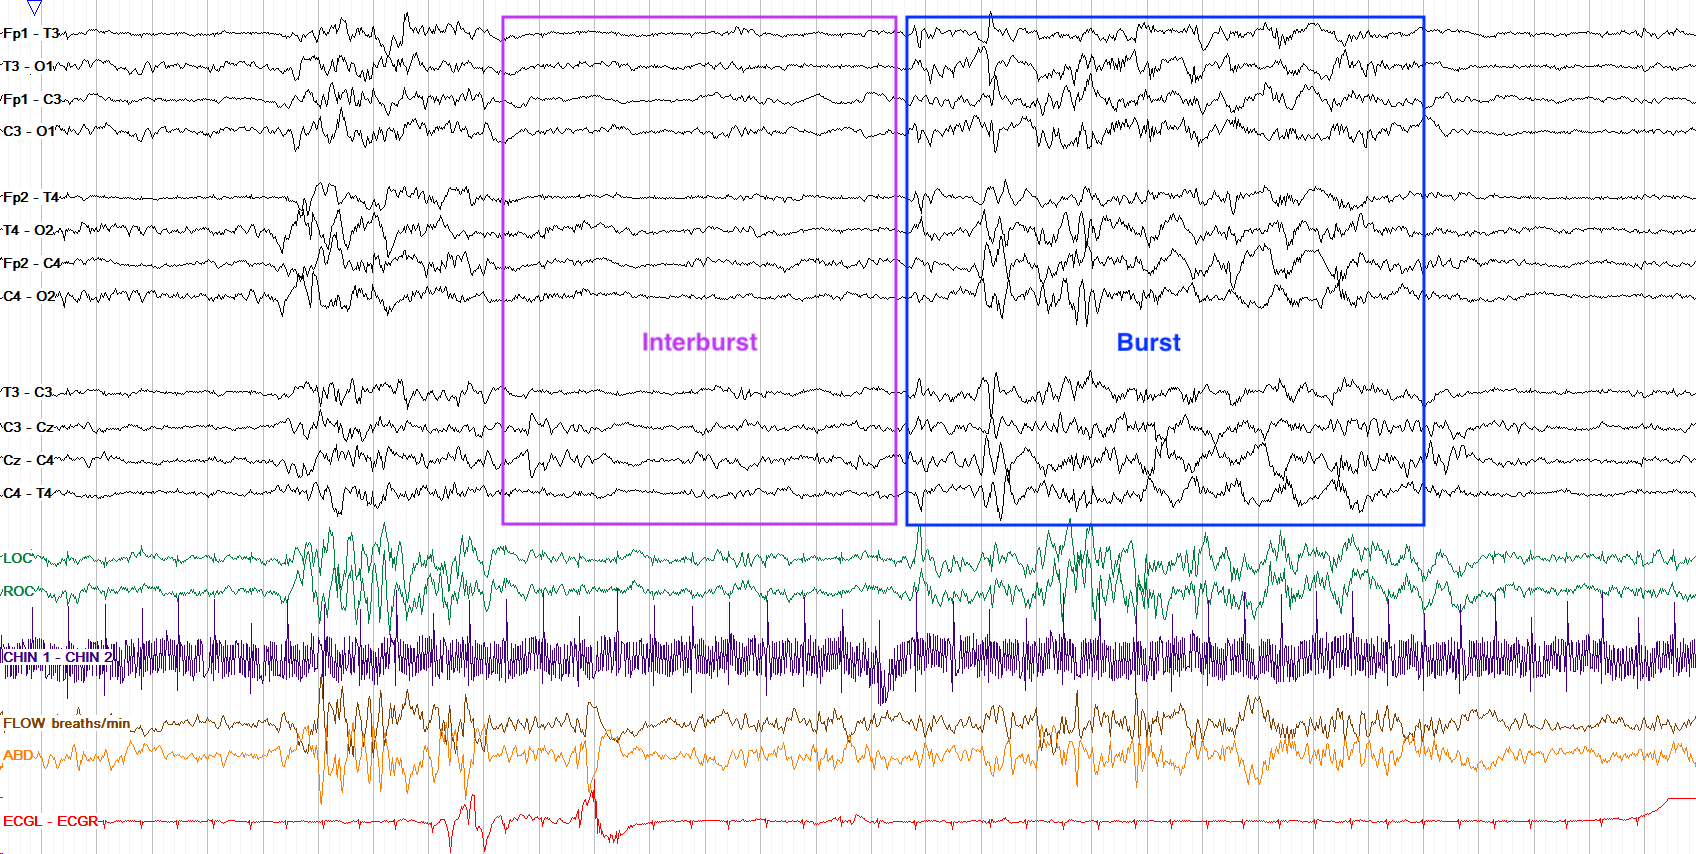

One of the most critical applications of EEG in newborn care is in the detection of seizures. Neonatal seizures can present differently than seizures in older children or adults, often going unnoticed during physical examinations. EEG provides a clear method of identifying these events, allowing for prompt treatment that can help prevent brain damage or other severe outcomes.

Interpreting EEG results in newborns requires specialized training since the brain wave patterns of infants can significantly differ from those of older children and adults. Neonatologists or pediatric neurologists analyze the recordings to identify any irregularities or abnormalities. Common interpretations include assessing the presence of seizures, determining brain maturity, and evaluating overall brain function.